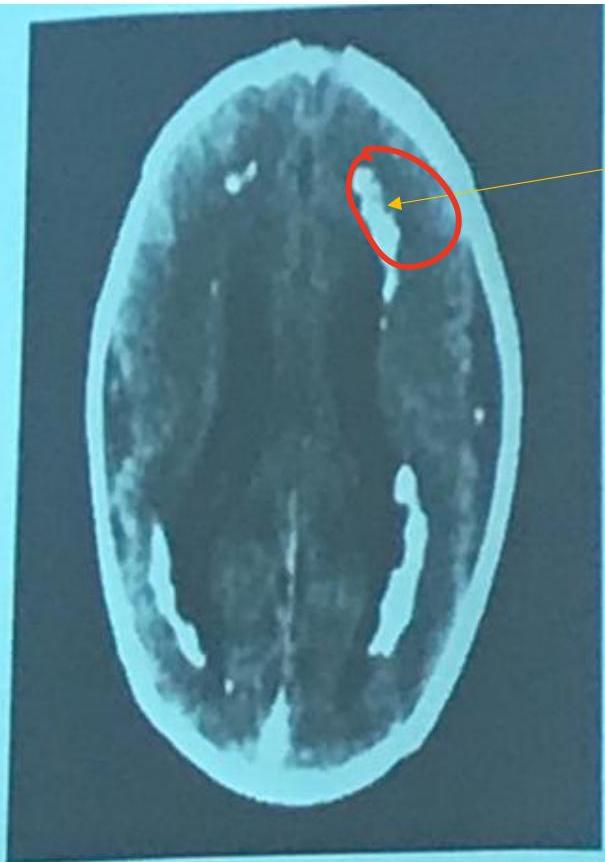

CMV Infection

Diagnosis? CMV.

CT finding? Periventricular calcification (vs Toxo which is scattered).

Findings:

- Microcephaly

- Jaundice

- Hearing loss

- Non-blanching rash

- Small for gestational age

- Calcification around the ventricles (C-shape)

Memory aid:

- C-shape calcification = CMV